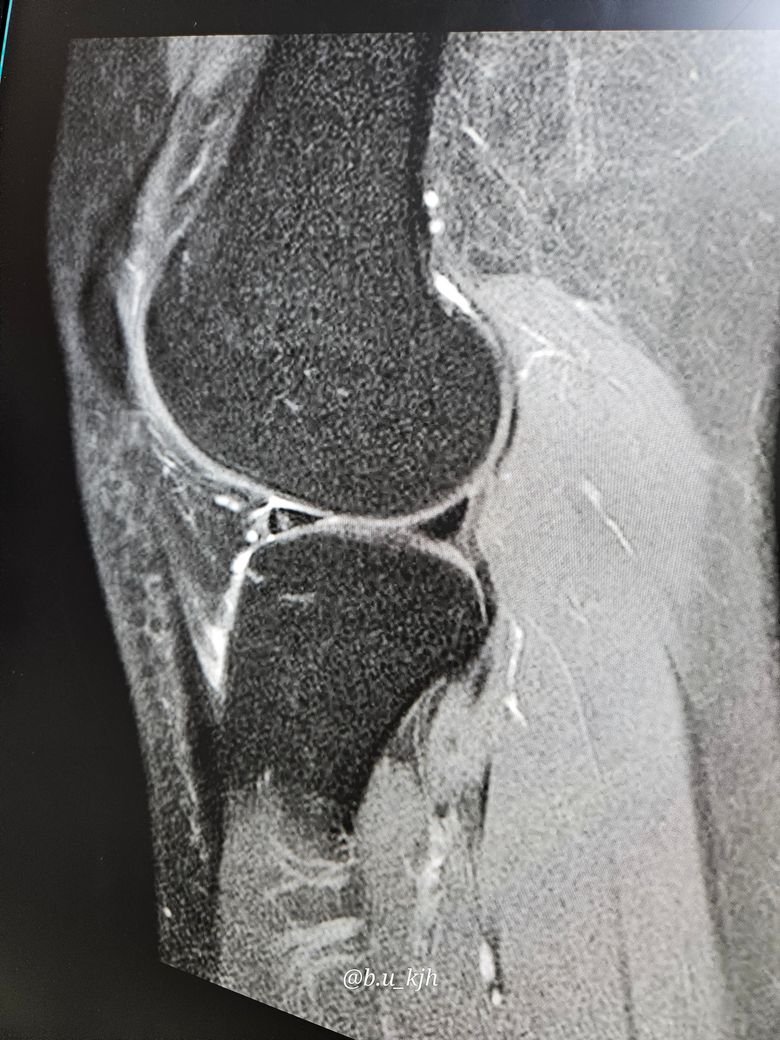

제 외측반월상연골판 찢어짐이라는데 설명좀부탁드립니다.

반월상연골판 찢어짐이라는데 첫번째.의사는 피가.안통해서 붙지않는다하고 두번째 의사는 찢어진게 아니라하고 셋번째의사는 외측반월상연골판 찢어짐이라고하고 네번째의사는 찢어졌지만 심하지 않다면서 모든 의사가 비수술을 말하더군요. 근데 찢어짐마다 모양이 다르고 봉합술도 있다고하는게 수술하면 더 안좋은건가요?? 최후에 방법이라고만 들어서 판단이 되지않네요 사진도 같이 첨부합니다...한번 자세히 봐주세요.

현재 콘쥬란 주사 1회, 소염진통제+마취제 주사 1회 맞았습니다. 통증은 양쪽다 있고 mri사진은 오른쪽만찍었습니다.

• 1번 째 사진

사실 저정도 찢어짐 소견 + 임상적으로 보행이 가능하다 하면 수술하지 않고 보존적 치료를 더많이하게 됩니다. 지금 주사치료는 어느정도 하신것 같고, 약먹고 필요하면 물리치료 + 충격파 치료를 받아서 효과가 있다면 충격파 치료를 좀더 유지하거나 통증이 좀 줄어든 다음엔 재활치료를 하시는게 장기적으로 도움이 되겠습니다

외측반월상연골판은 무릎 바깥쪽의 충격오나화 구조물인데 찢어진 위치와 모양에 따라 자연 치유 가능성이 달라집니다 대부분 피가 통하지 않는 부위느 ㄴ자연 회복이 어려워 수술이 필요할 수 있지만 증상이 경미하거나 안정적이면 비수술 치료가 우선입니다!